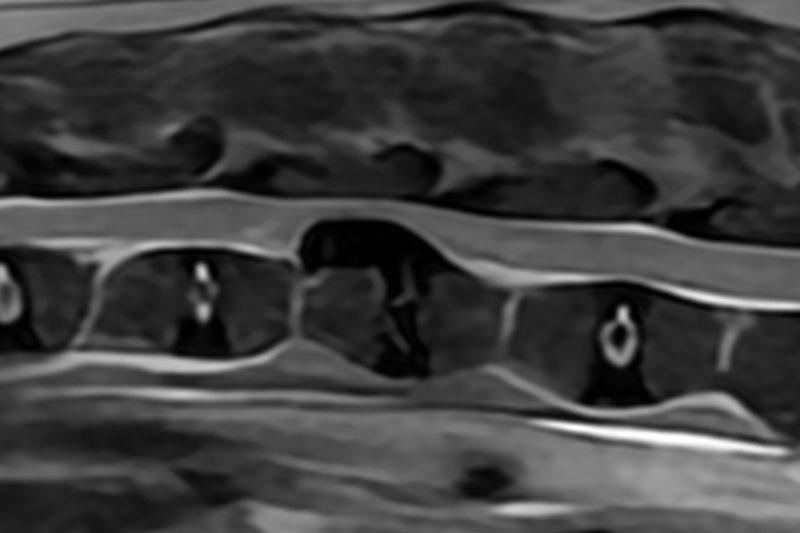

본 병원은 GE사의 1.5T 고해상도 자기공명영상장치(MRI)를 이용하여, 자기장을 이용한 비침습적 방식으로 뇌, 척수, 근골격계 등 다양한 연부조직을 정밀하게 영상화할 수 있습니다. MRI는 방사선을 사용하지 않아 반복 촬영에도 안전하며, 신경계 및 연부조직에 대한 탁월한 해상도를 제공하여 정확한 진단에 매우 유용합니다.

또한 본원의 MRI 장비는 GE사의 PROPELLER 기법을 도입하여 호흡이나 움직임에 따른 영상 왜곡을 최소화하면서도 검사 시간을 단축시켜, AI 기반 영상 처리 기술을 통해 노이즈를 줄이고 더욱 선명하고 명확한 영상을 획득할 수 있습니다. 이러한 기술적 강점을 바탕으로 마취 시간과 그에 따른 환자의 부담을 줄이면서도, 진단에 충분한 고화질 영상을 안정적으로 확보할 수 있습니다.

| 척수/신경계 | 디스크 탈출, 척수압박, 척수염, 척수종양 등 |